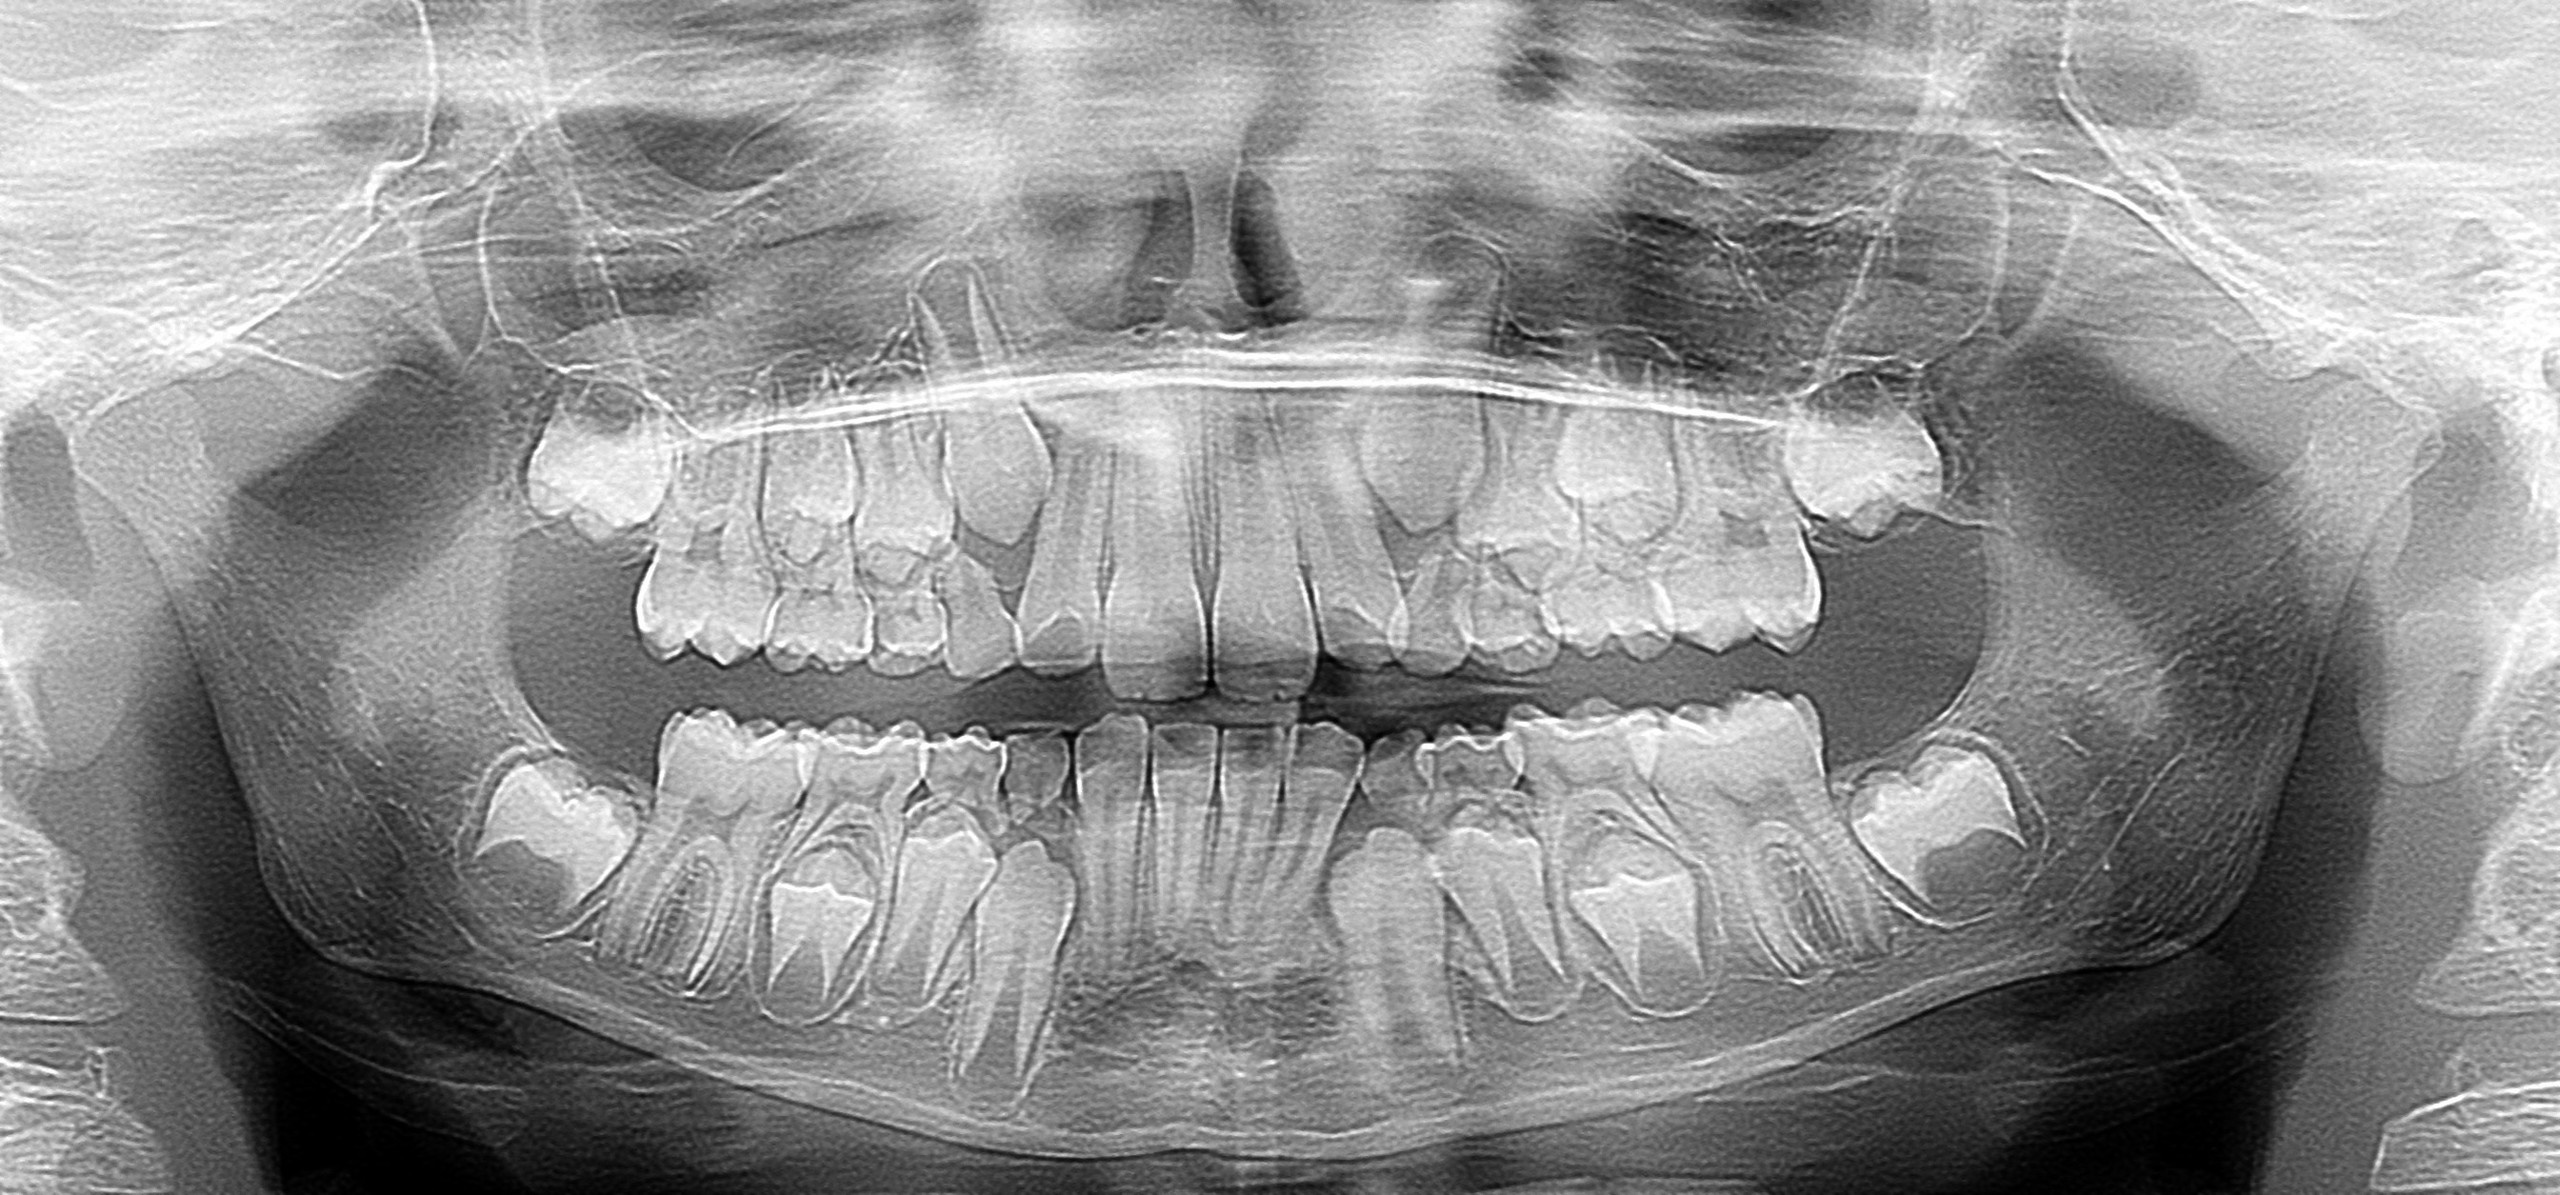

Ортопантомограмма (ОПТГ) ребёнка